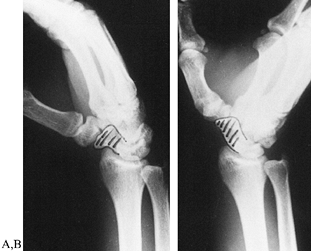

Figure 42.3. A,B:

Lateral radiographs of a normal wrist show the alignment of the radius, lunate, capitate, and metacarpals in neutral position and the movements of the radiocarpal and midcarpal joints with the wrist in slight and complete palmar flexion and dorsiflexion. Cineradiographic studies have shown that during the initial 30° of palmar flexion or dorsiflexion, motions at both radiocarpal and midcarpal joints are approximately equal. Further movements in either direction occur primarily at the midcarpal joint. The longitudinal axis of the scaphoid is at an angle of 45° to 60° to the longitudinal axis of the lunate with the wrist in neutral position. |